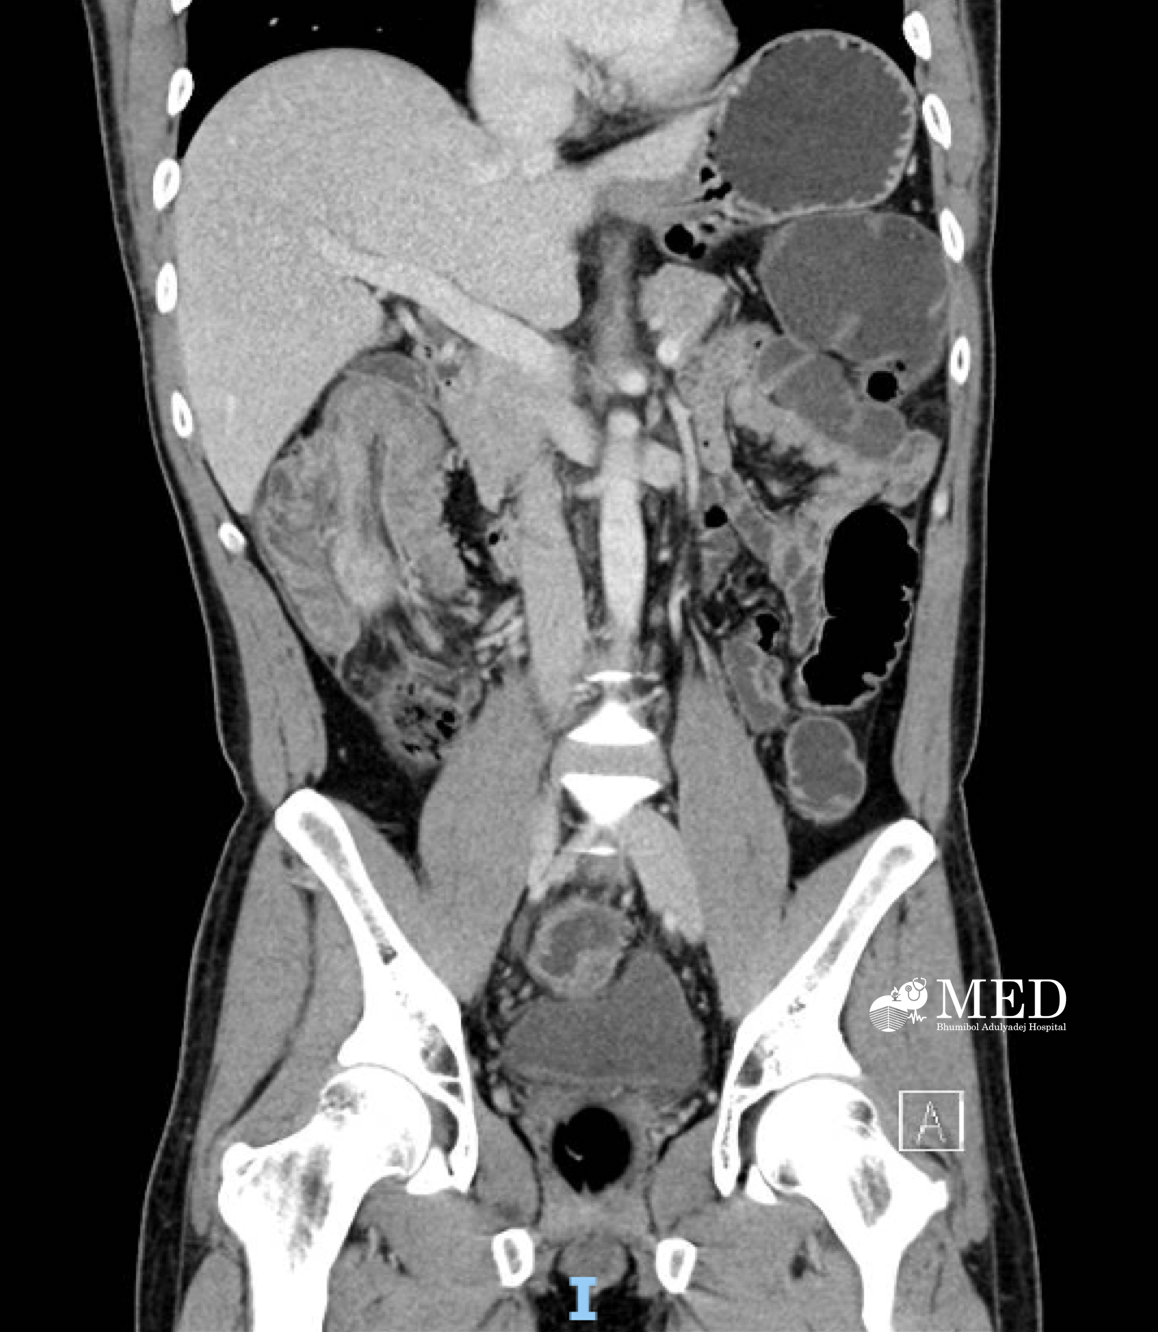

103. A 41-year-old man with abdominal pain and significant weight loss.

Case male 41 years old, no known underlying disease, presented with abdominal pain for 7 weeks and significant weight loss 4 kg in 2 months.

Question:  Please describe the film and give the diagnosis.